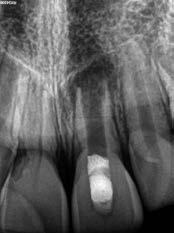

This element was not stimulated with the cold test and the radiographic image revealed an incomplete endodontic treatment (Figs. 1-2). The element seemed to present a suitable root length for a conservative restoration, but the apical position of the carious lesion and the proximity of the interdental bone ridge didn’t allow a correct rehabilitation with prosthetic crown, respecting the biological width.2

Figure 2: Initial radiograph showing endodontic dressing that had been present for some months, but the treatment was never completed. Note the depth of the caries lesion and the proximity of the interdental bone ridge, which may represent an obstacle for prosthetic rehabilitation.

The canal was sealed with a Thermafil™ cone (Dentsply Sirona) with an apical diameter of 0.30 mm (Figs. 3-4).